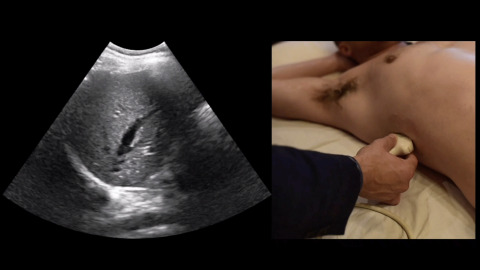

Lung Point

Jacob Avila demonstrates a lung point, which is finding of a pneumothorax.